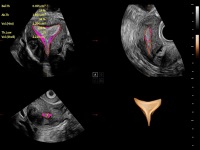

独有场成像发射技术

自适应聚合重建技术

在传统血流的基础上优化扫查和算法策略,能够更好的抑制组织信息,提炼红细胞运动信息,得到更高帧频,高灵敏度和分辨率的血流信号,还原更真实的血流动力学。

通过光照模型,使二维血流显示出立体的效果,增加血流的敏感性、成束性,减少外溢。可以和其他不同的血流技术联合使用,融合不同技术的优势。轻松应对微小血管,增强血流的立体效果,提升视觉敏感性。

通过创新的Matrix E自适应滤波算法,能有效滤除软组织和噪声信号,最大限度保留超低速微细血流的信号;结合超长时间域算法,极大提升细微血流的敏感性和空间分辨率,更真实的反应组织、包块的血流灌注情况。